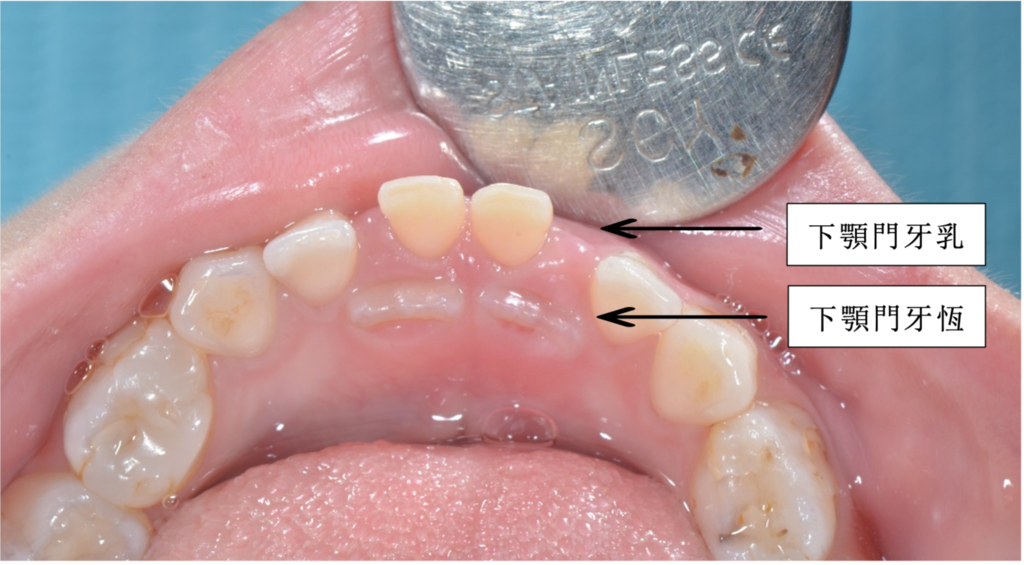

小朋友的下顎門牙長出來  偏舌側

乳牙還沒有掉  有需要拔掉嗎?

( A ) 首先 我們要知道下顎門牙的恆牙 牙胚位置在乳牙的舌側

因此長出來的時候會偏向舌側